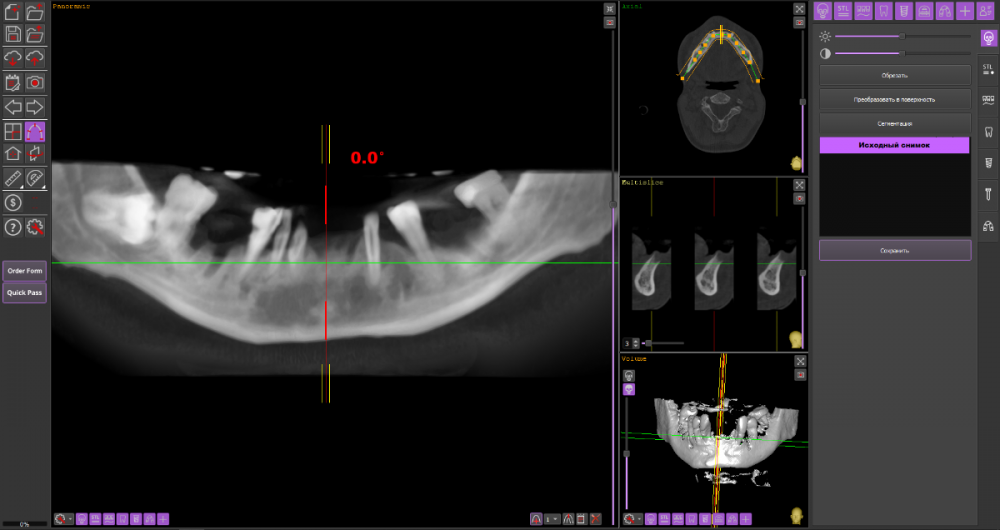

Сергей34 Опубликовано 13 октября, 2022 Автор Поделиться Опубликовано 13 октября, 2022 1 час назад, It'sGeorgy сказал: Вы правы. Перед установкой имплантатов снизу, зубы на верхней челюсти необходимо, как минимум, санировать и стабилизировать пародонтит. Само собой, необходимо учитывать состояние верхних зубов. Возможно, там уже санировать нечего и тогда крайне желательно делать обе челюсти вместе. Точнее без снимков сказать что-то невозможно. Вот верхняя челюсть. Кости как мне сказали тут почти нет и тут светит только протез обычный. https://we.tl/t-vedmhk4V7V Вот нижняя челюсть. https://we.tl/t-lwXRKsvL60 Тут как сказали можно всё на 4. Ссылка на комментарий

wladdX Опубликовано 14 октября, 2022 Поделиться Опубликовано 14 октября, 2022 верхняя челюсть нижняя челюсть 1 Ссылка на комментарий